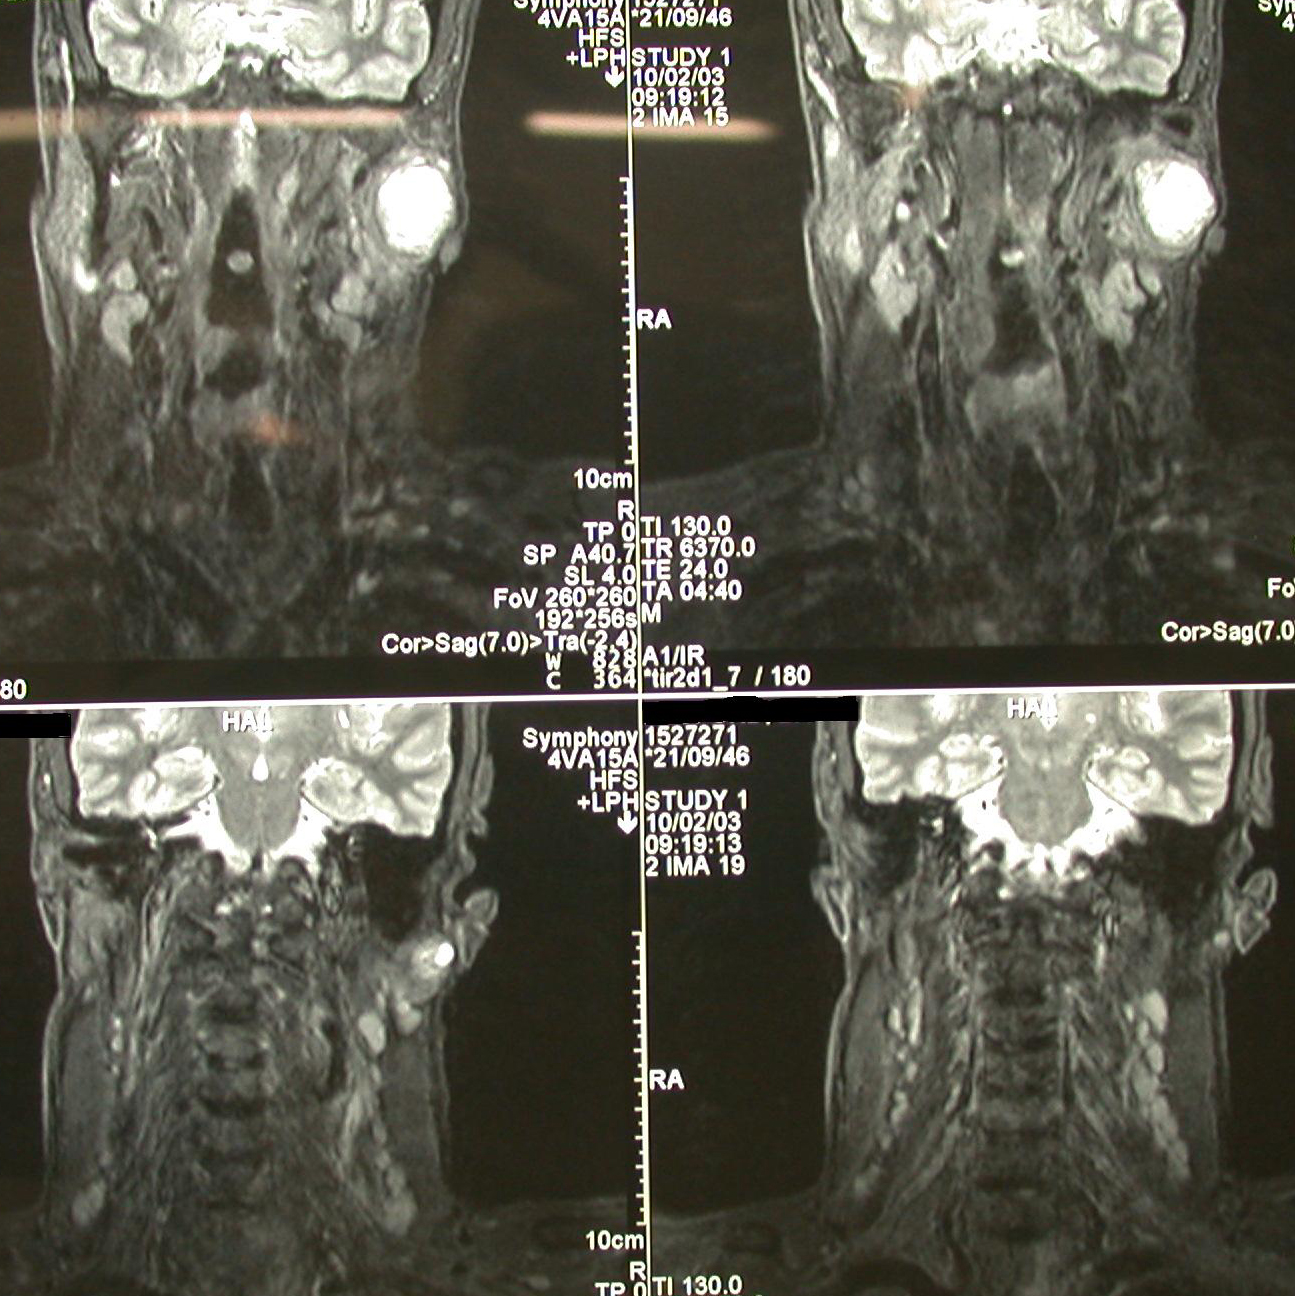

Figure 2: Four different views of an MRI scan, depicting a malignant tumour of the left parotid gland (large salivary gland in front of the ear) with involvement of the lymph nodes in the neck.